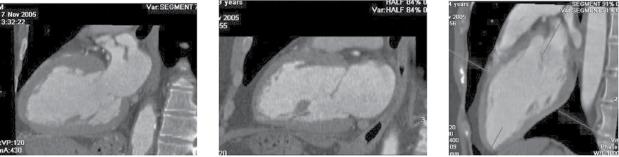

A 60‐year old woman with epigastric discomfort. Her medical history included a treadmill exercise test several years earlier because of negative T waves in V2 to V4 found on a routine

ECG (Figure). The ECG findings were considered a normal variant in a woman and the treadmill test was negative. The ECG shows sinus rhythm with mild biphasic T waves in V2 to V4.

Case 2

An echocardiogram was performed (left diastole, right systole)

Suggestions for diagnosis:

1) Congenital apical aneur ysm

2) Apical aneur ysm secondary to undiagnosed silent infarction

3) Apical congenital diverticulum

4) Apical hypertrophic cardiomyopathy

Correct answer: 1

The echocardiogram (of intermediate quality) detected an apical aneurysm. The ventricular aneurysm with a paradoxical expansion during systole and end‐systolic flow pattern from the ventricle to the aneurysm was better demonstrated with CMR (next figure, arrows) (Fiol M, et al. Int J Cardiovasc Imaging. 2015;31: 1261–1262). A “normal variant” is uncommon, but still possible, at the age of 60.